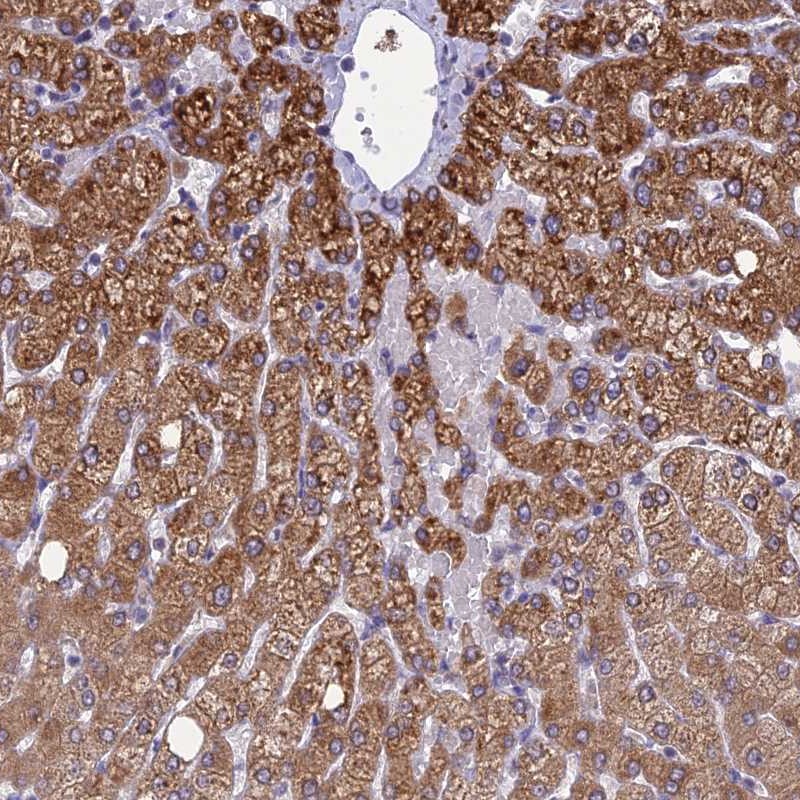

Immunohistochemical staining of human liver shows strong cytoplasmic positivity in hepatocytes.